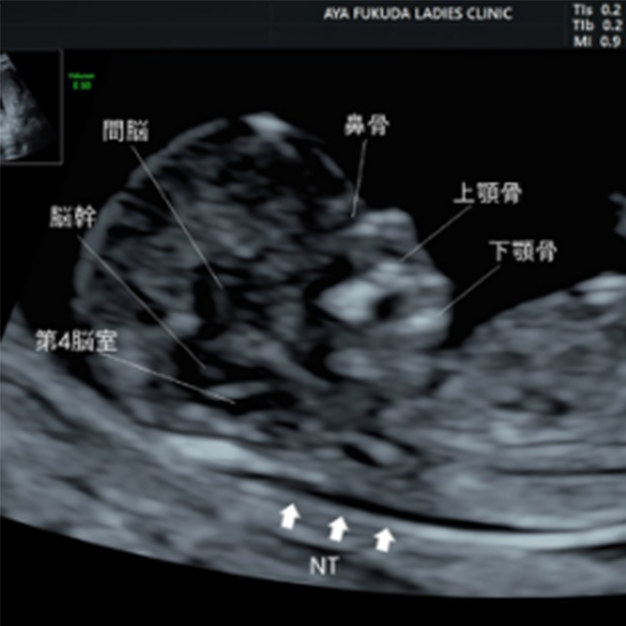

大阪市北区で胎児ドックをお探しならふくだあやレディースクリニックへ

02 妊娠初期 胎児の頸部浮腫 Nt 妊娠11 13週でcheck 深谷産婦人科 医学情報

妊娠初期超音波の出生前診断における役割 Fetal Skeletal Dysplasia Forum

大阪市北区で胎児ドックをお探しならふくだあやレディースクリニックへ